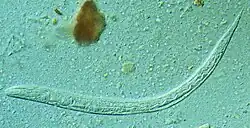

| First stage larva (L1) of S. stercoralis | |

Strongyloides (from Greek strongylos, round, + eidos, resemblance), anguillula, or threadworm is a genus of small nematode parasites, belonging to the family Strongylidae, commonly found in the small intestine of mammals (particularly ruminants), that are characterized by an unusual lifecycle that involves one or several generations of free-living adult worms.